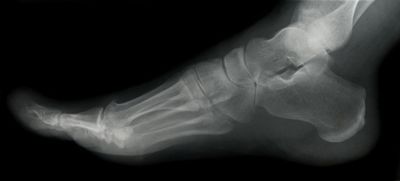

Custom foot orthotics are shoe inserts or insoles prescribed and fitted for a specific person by a qualified practitioner such as a podiatrist or chiropodist. Custom foot orthotics are designed to improve an imbalance in the foot by supporting and aligning the foot.

Custom foot orthotics are specially designed to be worn inside the shoe to control or correct abnormal foot function and/or accommodate painful areas of the foot. Properly designed custom orthotics fitted by a chiropodist may compensate for impaired foot function, by controlling abnormal motion across the joints of the foot. Custom foot orthotics should be comfortable from the onset, however, they may take some time to become totally comfortable while wearing them in appropriate shoes.

Custom foot orthotics help prevent some of the complications of the chronically unstable foot such as strained ligaments caused by abnormal pronation (turning out of the heel and forefoot).

Well designed and custom foot orthotics fitted by a chiropodist or podiatrist can also solve many related problems such as ankle and knee pain, pelvis, hip and spinal pain and even headaches, all by preventing misalignment of the foot (which can significantly alter the way bones move in relation to their joints).